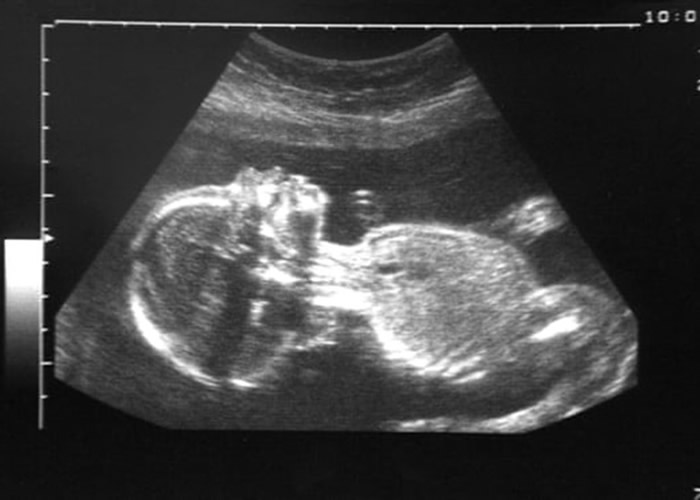

(蜘蛛网eeook.com报道)据东网:比利时哈瑟特大学的科学团队近日公布一项研究,发现孕妇的胎盘含有空气污染物。当孕妇吸入污染物后,胎儿亦变相会暴露于污染环境中,继而会导致婴儿流产、早产、出生时体重过轻等。

科学团队为25名不吸烟的孕妇进行测试,发现其胎盘全部都有黑碳悬浮粒子(black carbon)。而这些污染物所产物的黑碳悬浮粒子,相信是透过母亲呼吸渗入胎盘屏障;悬浮粒子的多少与孕妇的居住地有关。